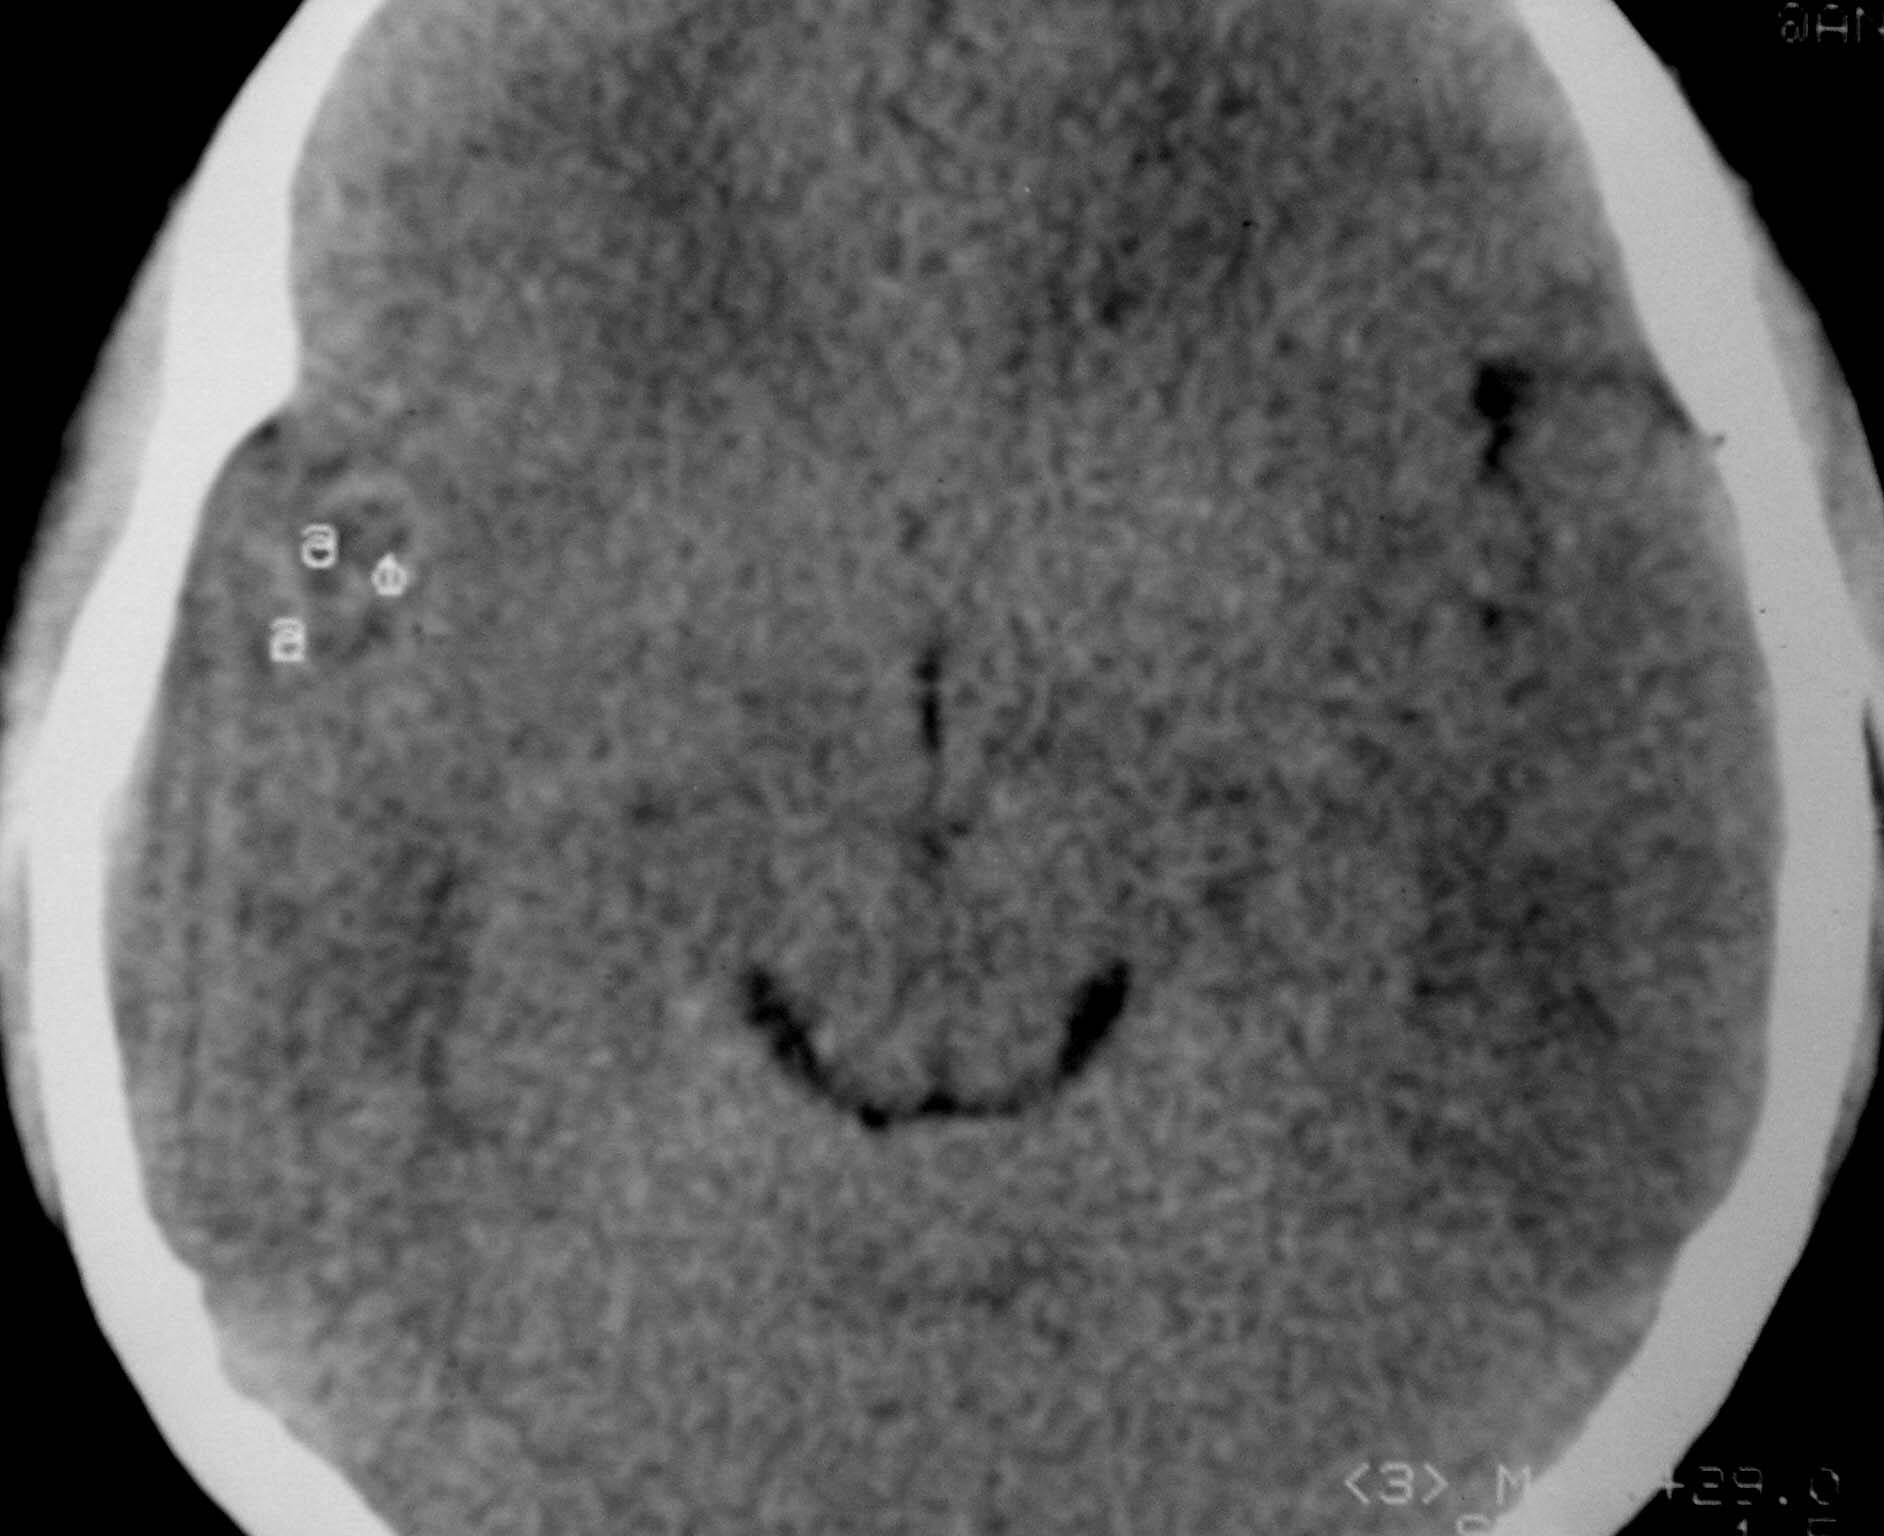

以下是引用余辉在2007-4-28 19:55:00的发言:[br]血管畸形?增强一下

以下是引用jw-830在2007-4-28 20:22:00的发言:[br]考虑血管畸形可能建议增强

以下是引用ysxyy在2007-4-29 21:14:00的发言:[br]像是假像,如果不放心可以偿试一下:[br]你用听眦线为基线扫一下,再用听眶线扫一下,就是说用不同的角度扫同一个地方;[br]看看有无变化,是不是有相同或相似的表现,即可鉴别;